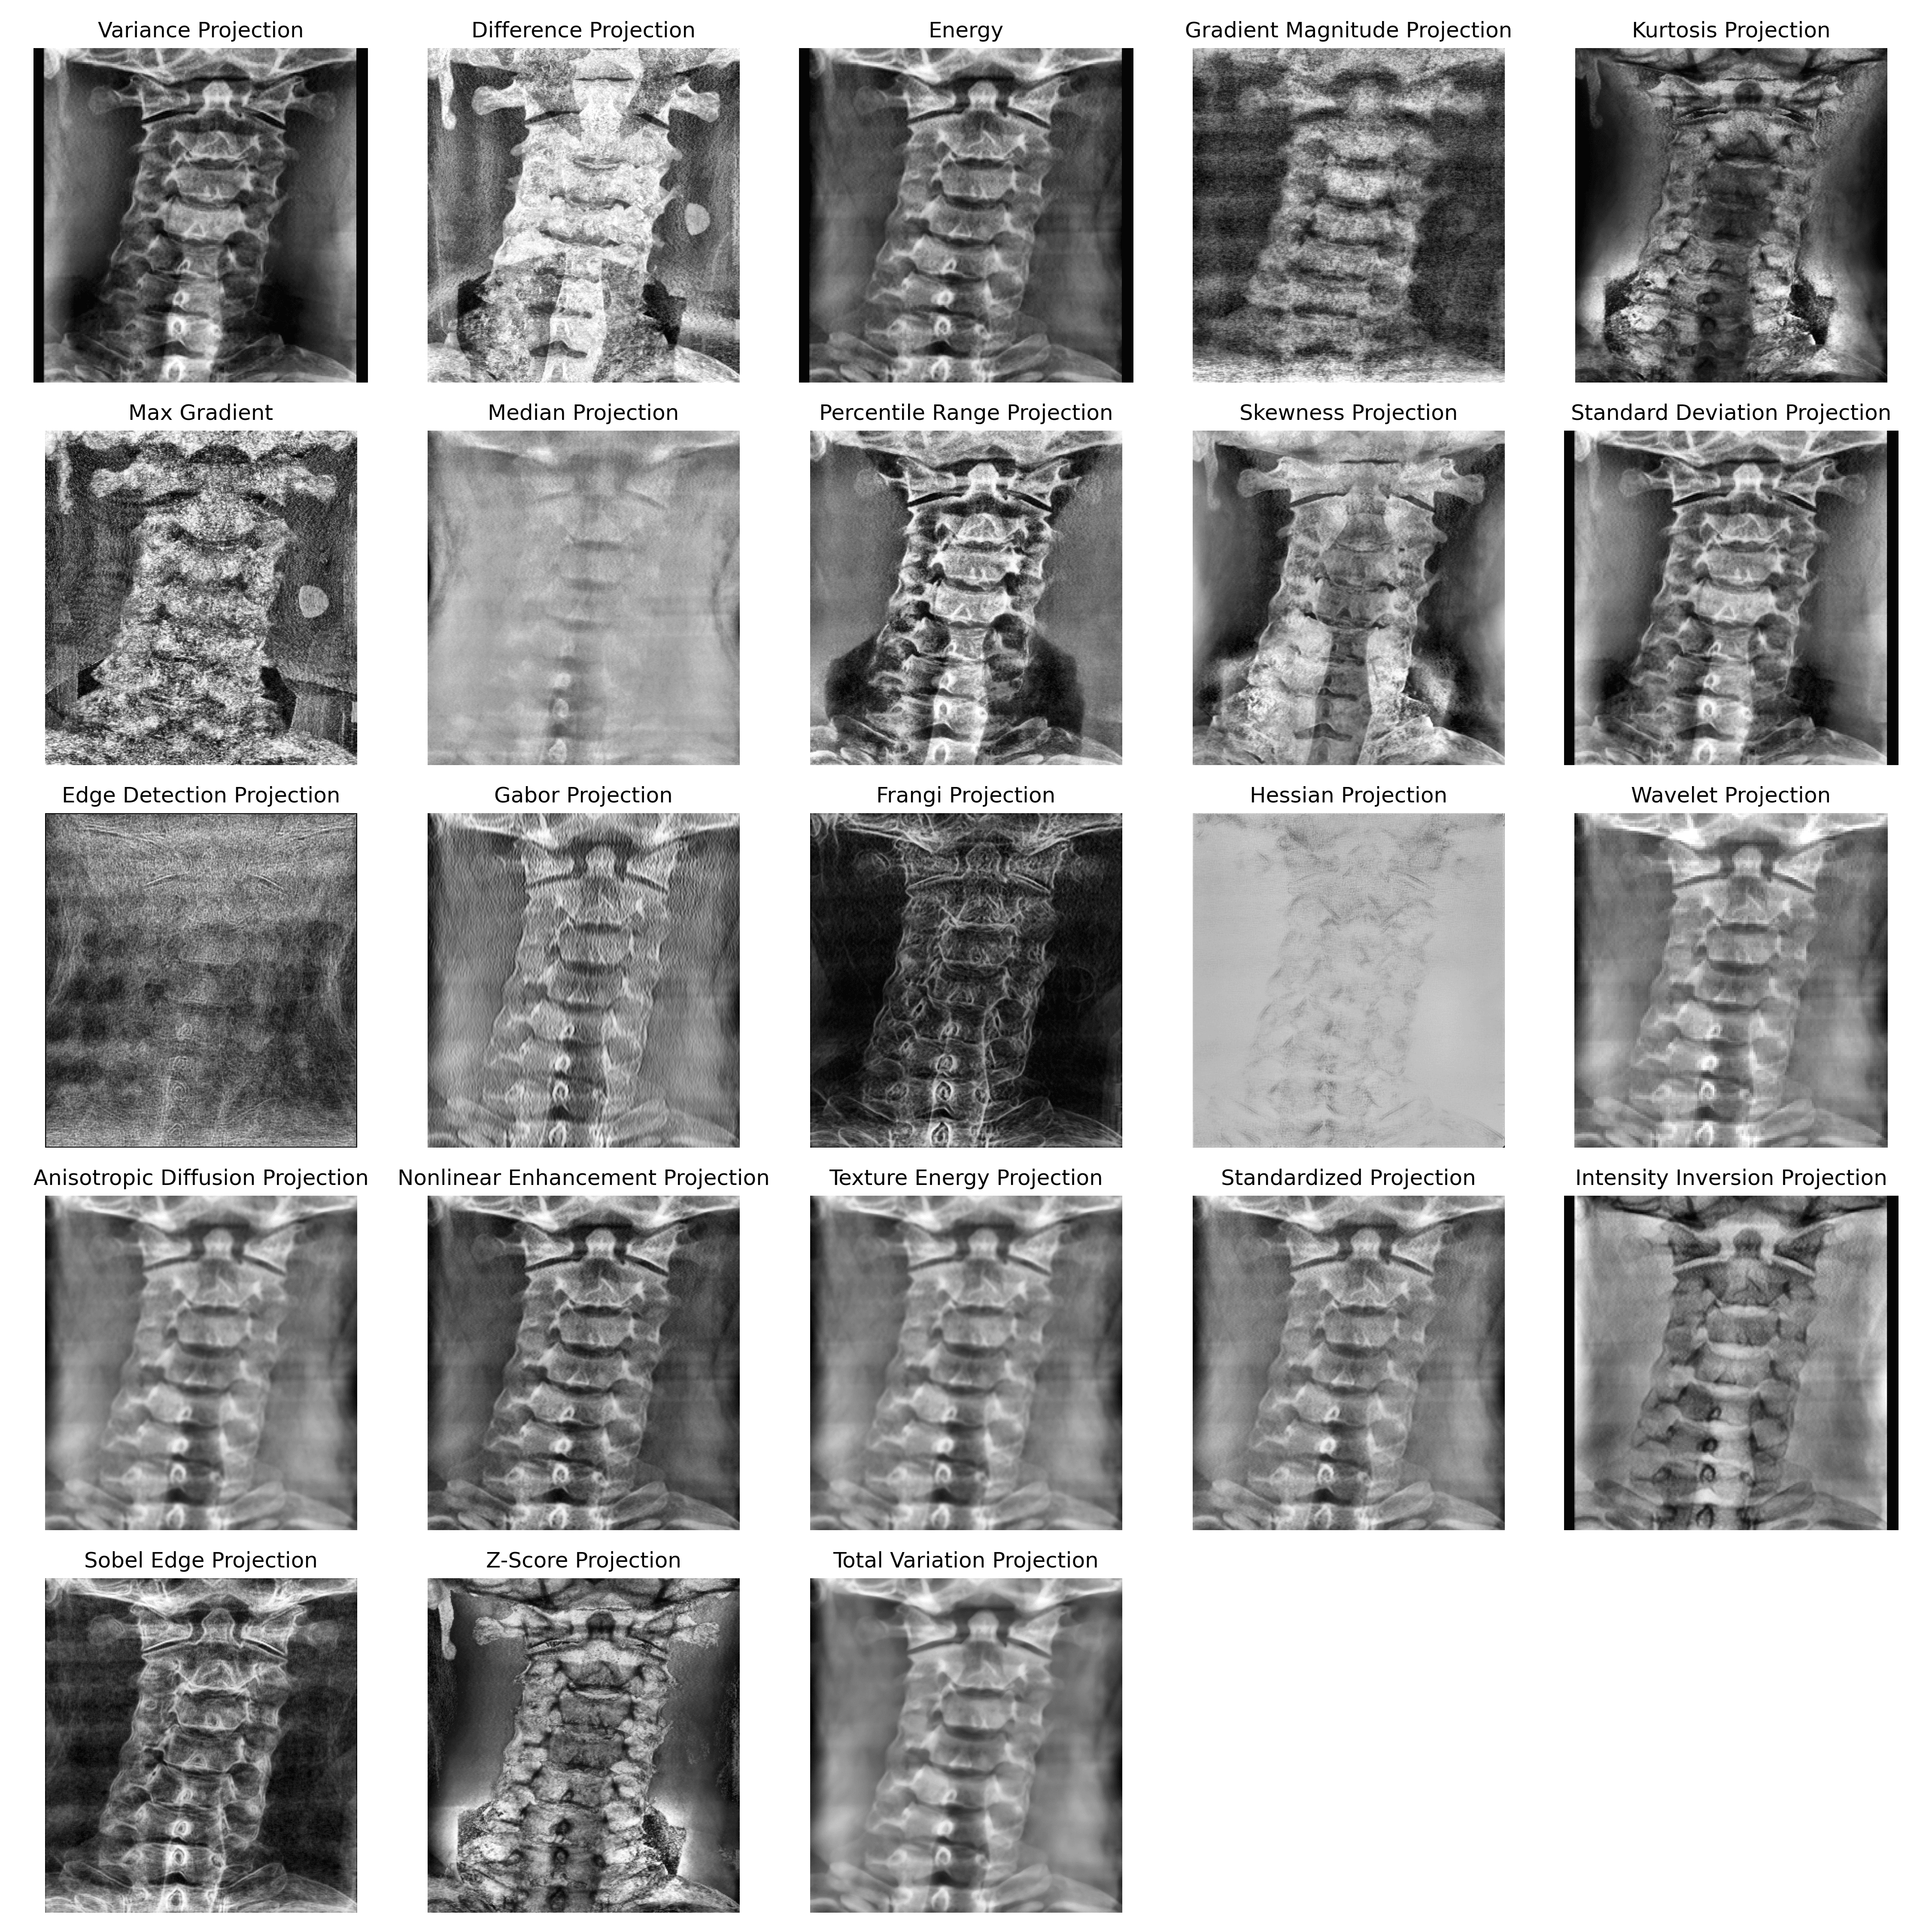

3.2 2D Projections of 3D CT Volume

To address the challenges of analyzing 3D CT volumes computationally, we employed 2D projection techniques that distill volumetric data into informative 2D representations. Orthogonal projections are computational techniques applied to volumetric imaging data such as CT to visualize the voxel intensities along specific views like axial, sagittal and coronal. Usage of different kinds of projection methods or functions enhances different anatomical features of the volume, the most popular of which is Maximum Intensity Projection (MIP) (Di Muzio and others, 2011) for analysis of CT volumes. It highlights maximum intensity pixels along the viewing direction, which is essentially a method of summarizing the volumetric data into a 2D plane. This summarization can be done using any function creating different projections. In this study, we have done an extensive investigation on several projection methods and their utility in cervical spine localization and vertebra segmentation. We have analyzed projections for both ROI detection and segmentation phases of the study and based on our investigation, we adopt variance projection for cervical spine ROI localization and energy projection for vertebra segmentation, as these projections were found to best preserve task-specific anatomical characteristics while maintaining computational efficiency.

Energy projection amplifies high-intensity anatomical structures, such as cortical bone, and enhances vertebral boundaries that are critical for accurate segmentation. This property is especially beneficial when generating projection-based representations for multi-label vertebra segmentation under anatomical overlap. Representative examples of variance and energy projections derived from the same cervical spine CT volume are shown in Figure 3, illustrating their complementary characteristics for ROI localization and vertebra segmentation, respectively. Comprehensive description of alternative projection operators, including their mathematical formulations and visual comparisons, are provided in the Supplementary Section S3.

To identify the most effective 2D representation for vertebra segmentation, we evaluated 23 projection techniques with the proposed DenseNet121 Unet on both sagittal and coronal views, using five fold cross validation. The vertebra specific IoU and Dice trends are summarized in Figure 14, while the full quantitative results, including HD95 and the global projection scores, are reported in Supplementary Table S4.

In Figure 14, the Energy projection (red curve) consistently traces the outer envelope of the radar plots across all vertebrae from C1 to C7 for both IoU and Dice, indicating that it dominates all other projections at every cervical level. Projections such as Inversion, Standard Deviation, and Variance form inner contours that remain close to Energy, reflecting competitive but slightly lower performance. In contrast, edge based projections like Gradient, Edge, and Hessian occupy the inner region of the plots with markedly smaller radii, showing reduced accuracy across all vertebrae. These patterns confirm that projections which preserve rich intensity statistics and bone contrast (for example Energy and variance based methods) are more informative for vertebral segmentation than those that rely mainly on sparse edge responses. Supplementary Figure S12 provides qualitative examples that mirror the radar plot, where Energy projection produces the most compact and anatomically faithful vertebral masks with fewer false positives than suboptimal projections.

Preprocessing ablations further showed that bone windowing before projection improved Dice and IoU by 1.82 and 2.60 percentage points respectively, while volume interpolation to at least 400 slices increased Dice by 5.51 points and reduced HD95 by 2.80 mm. Therefore, all subsequent experiments use Energy projection combined with bone windowing and volume interpolation as the default configuration for vertebra segmentation and downstream fracture classification. Additional supporting results are provided in Supplementary Section S6.